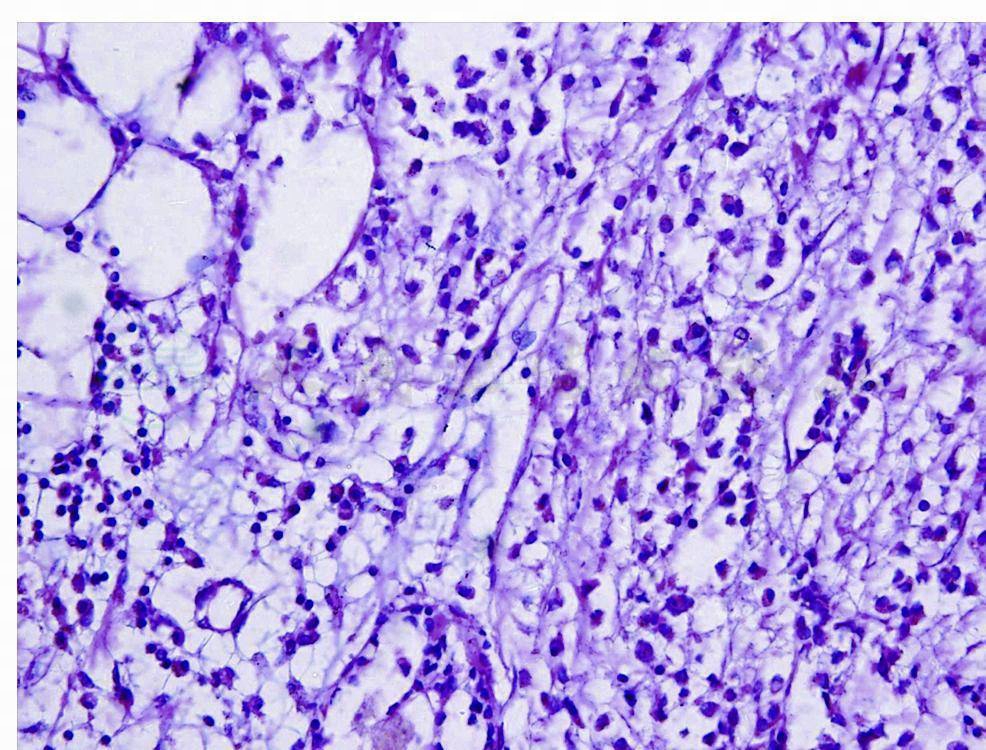

(二)实体型(弥漫型)

癌细胞呈弥漫片状分布,常将正常组织“淹没”,或者在脂肪组织中广泛浸润。细胞缺乏黏附性,小到中等大,大小一致,也可出现更明显的多形性,胞质内可有黏液和出现空泡,空泡内可见小红球,核通常和经典型的类似,也可有比较明显异型性,核分裂可比较多见。间质成分少,呈纤细束状(图3,图4)。仔细检查,通常在病变的边缘可见到经典型呈“列兵样”排列区。

图3 浸润性小叶癌(实体型)

腺泡周围有纤细的间质,癌细胞和经典型类似,胞质透明

图4 浸润性小叶癌(实体型)

浸润的癌细胞小而一致,细胞界限不清,核小而圆形,染色质细,核仁不清楚,缺乏核分裂和坏死,间质成分少,呈纤细束状